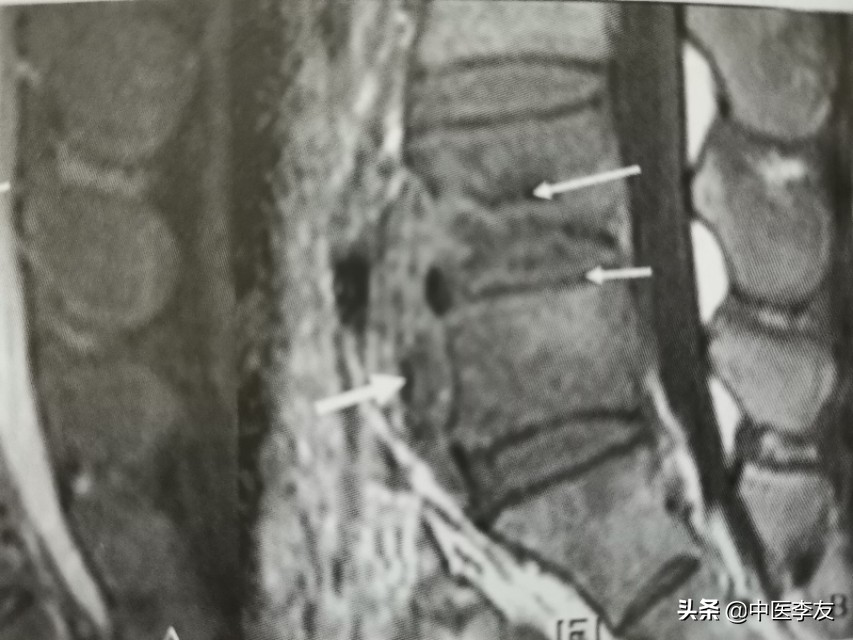

2.CT,表现与X线表现类似,但是有它自己特点:①能更清晰地显示骨质破坏,特别是较隐蔽和较小的破坏;②更容易发现死骨及病理骨折碎片;③增强扫描冷脓肿周边强化,内部无强化,可更好地了解冷脓肿的位置、大小,与周围大血管、组织器官的关系;④显示脓肿或骨碎片突入椎管内的情况

3.MRI,表现是显示脊椎结核病灶和范围最敏感的方法,可发现椎体内早期炎性水肿。病灶T1WI表现为低信号,T2WI多表现为混杂高信号;GD-DTPA增强不均匀强化。脓肿和肉芽肿在T1WI上呈低信号,T2WI多为混杂高信号,部分均匀高信号,增强检查肉芽肿不均匀,均匀强化,脓肿壁薄且均匀的环状强化。